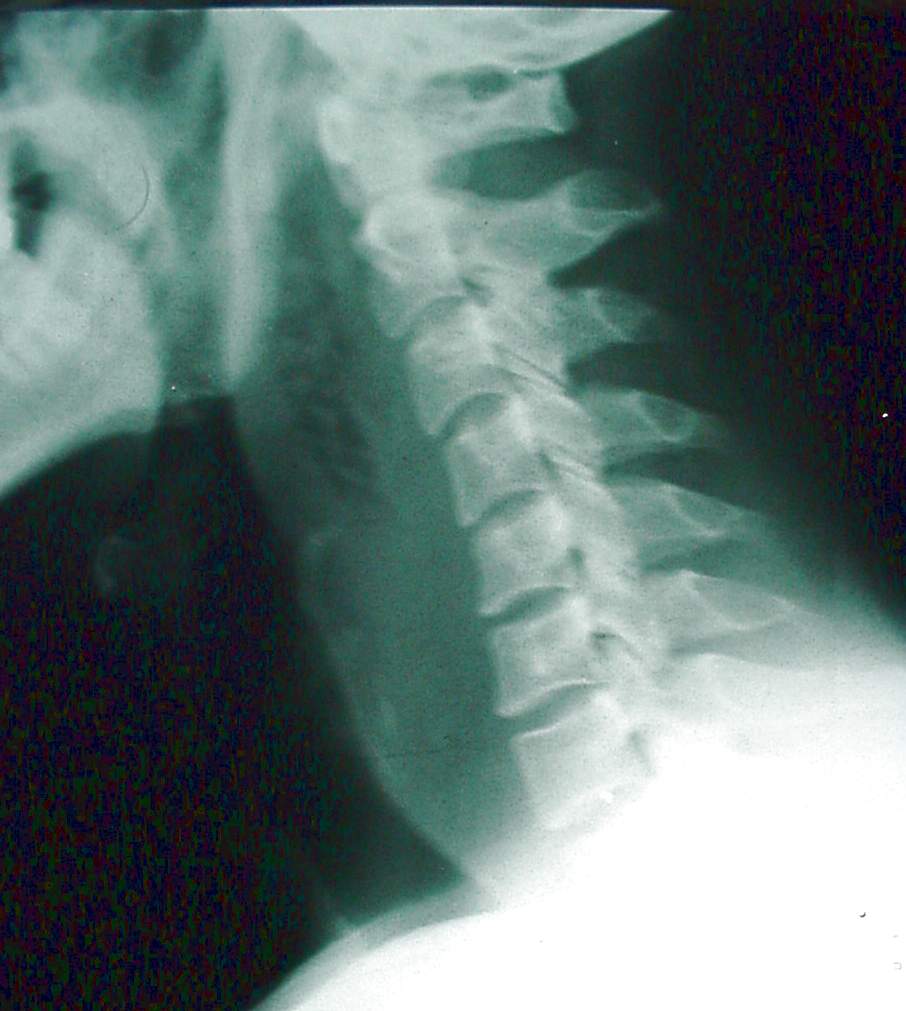

Pharynx and Esophagus Clinical Photos for Static Stations